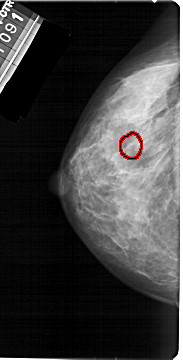

A_1392_1.LEFT_CC

LEFT_CC LINES 5386 PIXELS_PER_LINE 2731 BITS_PER_PIXEL 12 RESOLUTION 43.5 OVERLAY

FILE: A_1392_1.LEFT_CC.OVERLAY

TOTAL_ABNORMALITIES 1

ABNORMALITY 1

LESION_TYPE CALCIFICATION TYPE PLEOMORPHIC DISTRIBUTION CLUSTERED

ASSESSMENT 4

SUBTLETY 2

PATHOLOGY BENIGN

TOTAL_OUTLINES 1